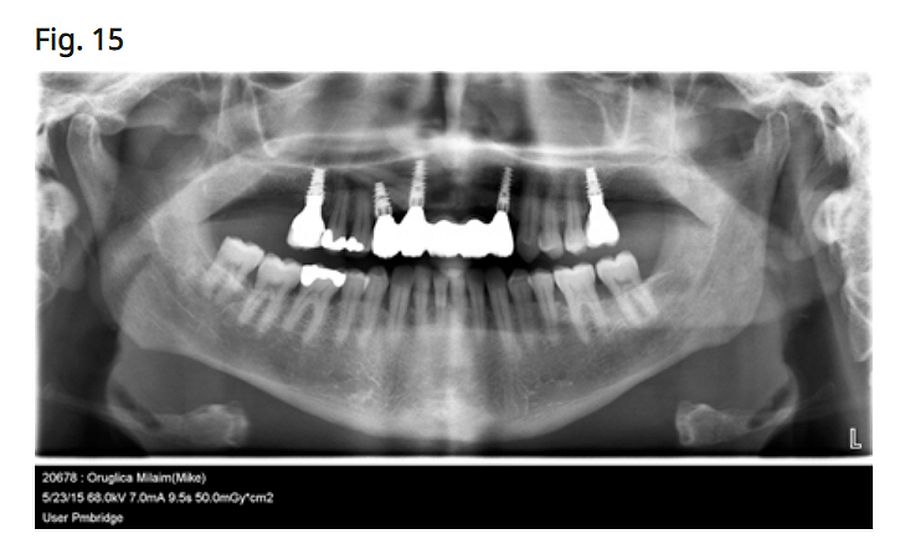

Impacted canine extraction + implant + graft DL Oral Surgery Dental Implant For Impacted Canine this treatment plan represented a less invasive option that was not explored by other clinicians during a number of previous consultations which involves placement of dental implants directly through a maxillary impacted canine. From this search, 28 articles were collated that satisfied the. placing dental implants through impacted teeth may offer a possible. the maxillary canine is. Dental Implant For Impacted Canine.